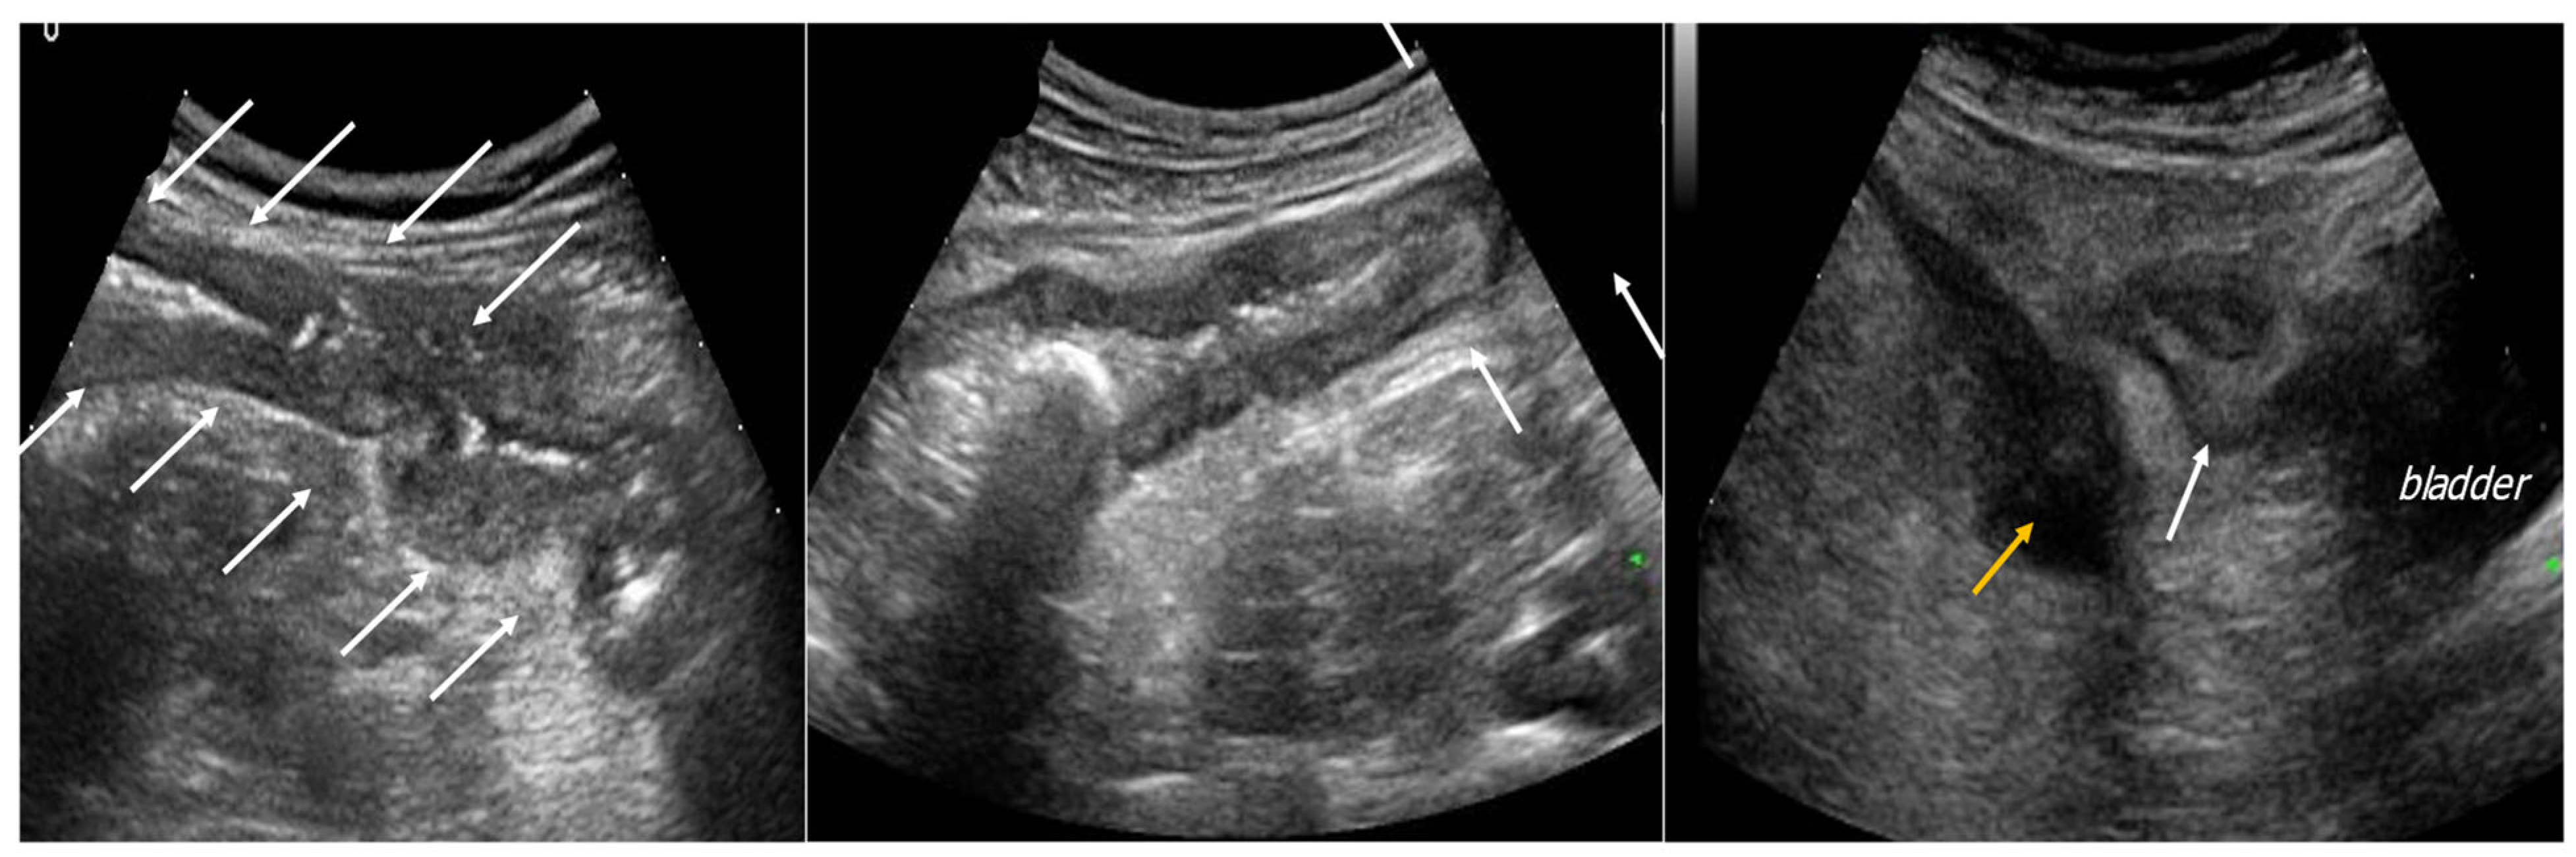

4. Acute Appendicitis

5. Acute Diverticulitis